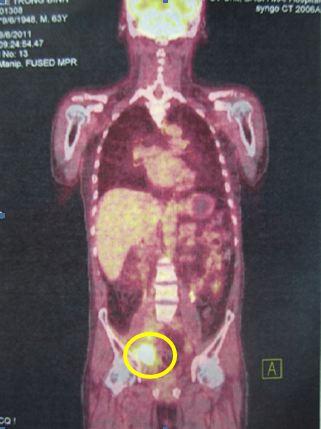

Bệnh nhân được chỉ định chụp PET/CT toàn thân có mô phỏng với kết quả hai khối tổn thương tăng hấp thu FDG mạnh với SUV tăng rất cao vùng hố chậu bên phải:

Hình ảnh PET/CT cắt dọc: Vùng tổn thương trong vòng màu vàng